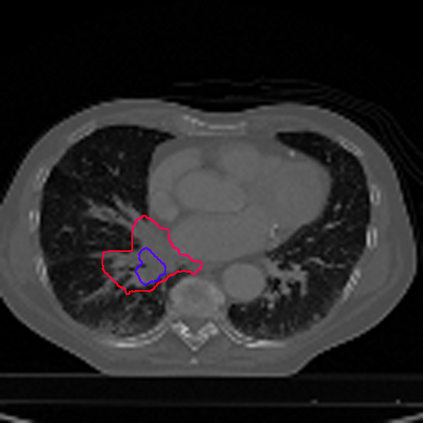

Lung cancer is a leading cause of death in most countries of the world. Since prompt diagnosis of tumors can allow oncologists to discern their nature, type and the mode of treatment, tumor detection and segmentation from CT Scan images is a crucial field of study worldwide. This paper approaches lung tumor segmentation by applying two-dimensional discrete wavelet transform (DWT) on the LOTUS dataset for more meticulous texture analysis whilst integrating information from neighboring CT slices before feeding them to a Deeply Supervised MultiResUNet model. Variations in learning rates, decay and optimization algorithms while training the network have led to different dice co-efficients, the detailed statistics of which have been included in this paper. We also discuss the challenges in this dataset and how we opted to overcome them. In essence, this study aims to maximize the success rate of predicting tumor regions from two dimensional CT Scan slices by experimenting with a number of adequate networks, resulting in a dice co-efficient of 0.8472.